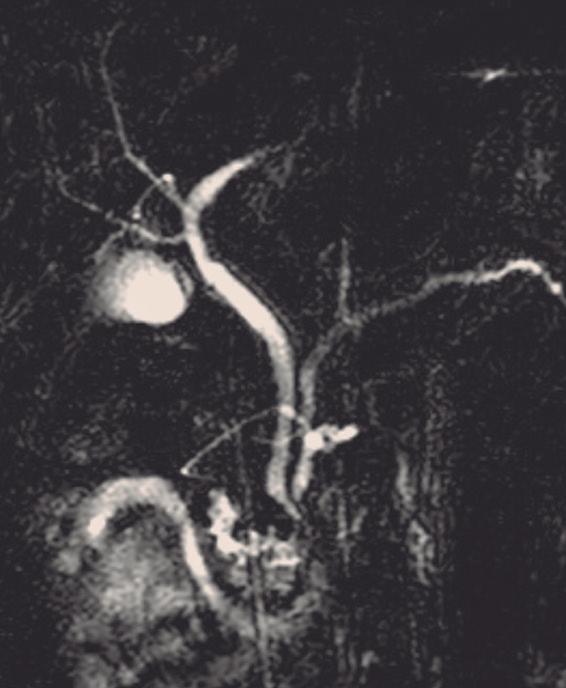

Páncreas divisum

Es la anomalía del desarrollo pancreático más frecuente, presente en 4 a 14% de la población según lo publicado en diferentes series.5

En esta condición hay una falta de fusión de los conductos del páncreas dorsal con el ventral, por

ende, la mayoría de las secreciones de la glándula desembocarán en la papila menor. Se han descripto tres subtipos de páncreas divisum. Tipo 1 o clásico, con falta completa de fusión, pudiendo identificarse ambos conductos claramente separados; tipo 2, donde el

conducto dorsal es dominante y drena en la papila menor, mientras que el conducto de Wirsung (páncreas ventral) está ausente; y tipo 3 o funcional, donde hay una rama comunicante filiforme entre ambos conductos (Figura 2). 6, 7

Los individuos con páncreas divisum suelen ser asintomáticos y diagnosticados incidentalmente en estudios de colangio-RM realizados por otros motivos (Figura 3). Se ha descripto su potencial rol como desencadenante de eventos de pancreatitis aguda (PA) y pancreatitis aguda recurrente (PAR). La hipótesis es que la papila menor, más pequeña, es insuficiente para permitir el drenaje adecuado del volumen de secreciones originadas en el páncreas corpocaudal, que habitualmente derivan hacia la papila mayor. Actualmente se acepta que la PAR es

una condición de origen multifactorial y que el páncreas divisum actúa como cofactor, habitualmente asociado a otras entidades, como son las mutaciones genéticas (genes CFTR, PRSS1). La sola presencia de páncreas divisum como “gatillo” de pancreatitis es controversial, fundamentalmente debido a que no se ha demostrado mayor prevalencia de esta condición en pacientes con PA, comparativamente con la población general.8, 9 En la colangio-RM podemos encontrar algunos elementos imagenológicos que sugieren un posible au-

Figura 3. Páncreas divisum. Colangiopancreatografía por resonancia magnética

A B C

A) Subtipo 1. Las flechas señalan al conducto pancreático principal, que drena sus secreciones en la papila menor. La cabeza de la flecha señala el conducto de Wirsung desembocando en la papila mayor. B) Subtipo 2. CPP desembocando en la papila menor en ausencia de un conducto definido del páncreas ventral. C) Subtipo 3. La flecha señala una diminuta comunicación entre los conductos del páncreas dorsal y ventral.